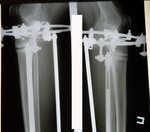

30 дней с момента операции.

РЕНТГЕН НА 30 - ЫЙ ДЕНЬ С МОМЕНТА ОПЕРАЦИИ.

РЕНТГЕН ДО ОПЕРАЦИИ

Рентген в 121 день. Снимать аппараты рановато, ждём ещё месяц. Делаем повторный рентген и смотрим. Можно снимать не 10 апреля, а на несколько дней раньше. кушайте творог, мясо, кальций, холодец, мумиё (как учили в клинике) и позитивное настроение! 04000000.

Рентген перед снятием аппаратов.

в аппаратах пред снятием.